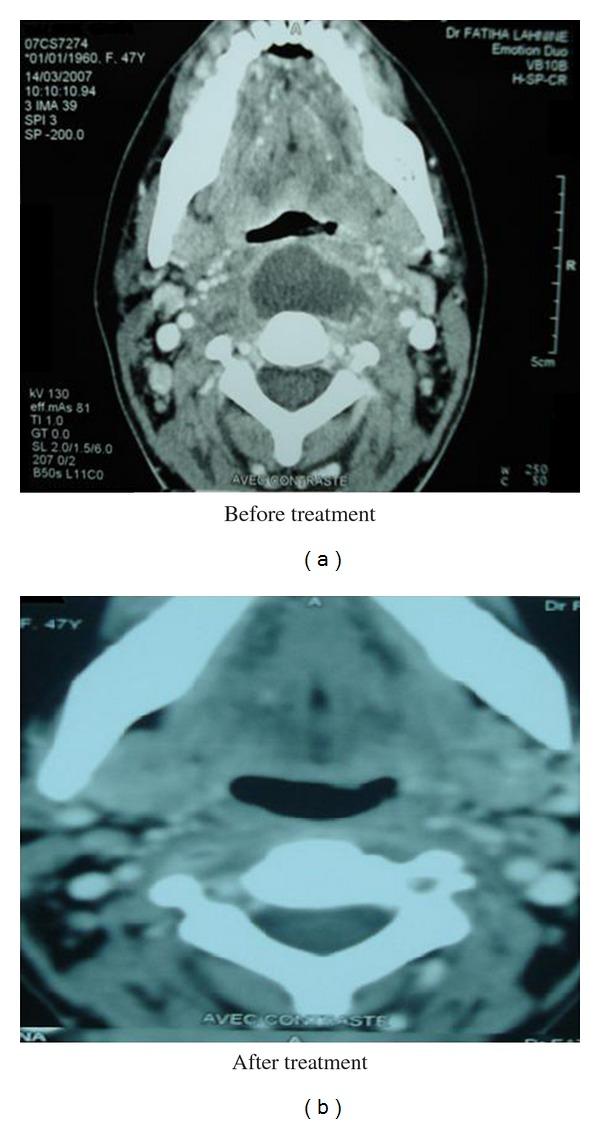

Retropharyngeal abscesses are rare in adults. They occur mostly in immunocompromised patients or as a foreign body complication. We report 5 cases of retropharyngeal abscess collected in the ENT Department of CHU Mohammed VI of Marrakech, during a two-year period (December 2008 to December 2009). Local trauma by foreign body ingestion was the aetiology in four patients. The presenting symptoms, for all patients, were fever, odynophagia, torticollis, and trismus, and the clinical examination showed bulging of the posterior wall of the oropharynx. The radiography of cervical spine showed prevertebral thickening in all cases, this thickening was associated with an aspect of vertebral lysis of the fourth cervical vertebra in one case. A CT scan was performed in all our cases and showed features of retropharyngeal abscess which was associated, in one case, with spondylodiscitis. The biological assessment found one case of diabetes. The intradermal reaction to the tuberculin was clearly positive in one case. Endobuccal abscess puncture was practiced in 4 cases; only one organism was identified by culture: Staphylococcus aureus treatment was based on triple intravenous antibiotics and anti-Koch's therapy (in one case), and the surgical drainage under general anesthesia was also performed in the case of the diabetes patient which required also the correction of hyperglycemia in intensive care unit. The outcome was good in all our patients. The diagnosis of retropharyngeal abscess can be difficult and one must seek a comorbidity; a tuberculosis aetiology must be considered in countries with a high prevalence. The management of these cases is based on antibiotics and surgical drainage.

咽后脓肿在成人中较为罕见。它们大多发生在免疫功能低下的患者中,或作为异物并发症出现。我们报告了在马拉喀什穆罕默德六世大学医院耳鼻喉科在两年期间(2008年12月至2009年12月)收集的5例咽后脓肿病例。4例患者的病因是异物吞食导致的局部创伤。所有患者的主要症状为发热、吞咽痛、斜颈和牙关紧闭,临床检查显示口咽后壁膨出。颈椎X线片在所有病例中均显示椎体前增厚,其中1例增厚与第四颈椎椎体溶解表现相关。我们所有病例均进行了CT扫描,显示咽后脓肿特征,其中1例与脊椎椎间盘炎相关。生物学评估发现1例糖尿病患者。1例患者结核菌素皮内反应明显阳性。4例患者进行了口内脓肿穿刺;培养仅鉴定出1种微生物:金黄色葡萄球菌。治疗基于三联静脉抗生素和抗结核治疗(1例),对于糖尿病患者还在全身麻醉下进行了手术引流,该患者在重症监护病房还需要纠正高血糖。我们所有患者的预后良好。咽后脓肿的诊断可能困难,必须寻找合并症;在患病率高的国家必须考虑结核病因。这些病例的管理基于抗生素和手术引流。